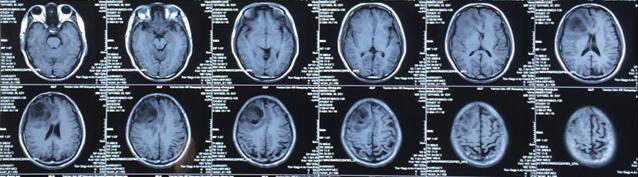

患者王某某,男,53歲,因“間斷頭痛半月”入神經(jīng)內(nèi)科十二病區(qū),發(fā)現(xiàn)顱內(nèi)占位后轉(zhuǎn)入神經(jīng)外科。既往患者有肺Ca病史,于一年前行手術(shù)治療。頭顱影像學(xué)診斷膠質(zhì)瘤?轉(zhuǎn)移瘤待排。2016年6月29日在3.0T磁共振定位后,劉增強副主任與其團隊為患者實施了立體定向腦內(nèi)病變活檢術(shù),此患者病灶為囊實性,手術(shù)難度較大,而一旦囊液流失則會發(fā)生腦組織漂移,導(dǎo)致靶點移位,因此手術(shù)計劃制定尤為重要,入顱點為右額部,穿刺后首先達到腫瘤實性部分,獲取病灶標本后,抽出部分囊液以緩解患者高顱壓癥狀,經(jīng)過精細的手術(shù)操作,最終成功獲取腫瘤標本,并且抽出約20ml腫瘤液,患者情況穩(wěn)定,術(shù)后兩小時即下床活動。

術(shù)后冰凍切片報告考慮轉(zhuǎn)移瘤,我院石蠟病理結(jié)果為少許低分化癌組織,結(jié)合病史符合肺癌腦轉(zhuǎn)移。